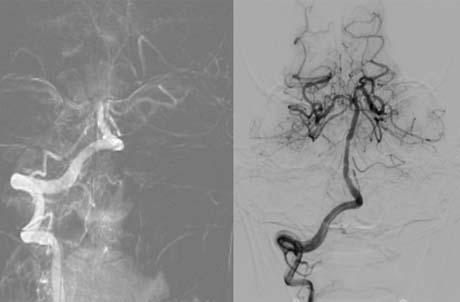

在急诊导管室内,神经外科宋立新副主任医师主刀,燕鹏主治医师协助操作,凭借娴熟的技术,通过患者股动脉置入直径仅2毫米的微导管。借助高清数字减影血管造影(DSA)的实时导航,取栓支架犹如精准的"深海探测器",直达颅内血管堵塞部位。当支架张开捕获血栓的瞬间,屏幕上原本中断的血流轨迹重新跃动。"通了!"随着主刀医生的宣告,堵塞血管的血栓被完整取出,这场毫米级血管内的"拆弹行动"圆满成功。

3月20号,70岁的孙先生同样突然出现右侧肢体活动不利、言语不利的症状,右腿丧失活动能力,肌力为0级。患者入院时距离发病已将近8个小时,完善卒中一站式CT显示患者左侧大脑前动脉起始段完全闭塞,当时已经没有静脉溶栓的机会,介入取栓手术是患者恢复健康的唯一希望。宋立新副主任医师负责取栓手术主要操作,带领神经介入团队,通过负压抽吸血栓技术,顺利打通闭塞血管,术后2天,患者右腿肌力恢复到4级,术后10天出院时患者肢体力量接近正常水平。